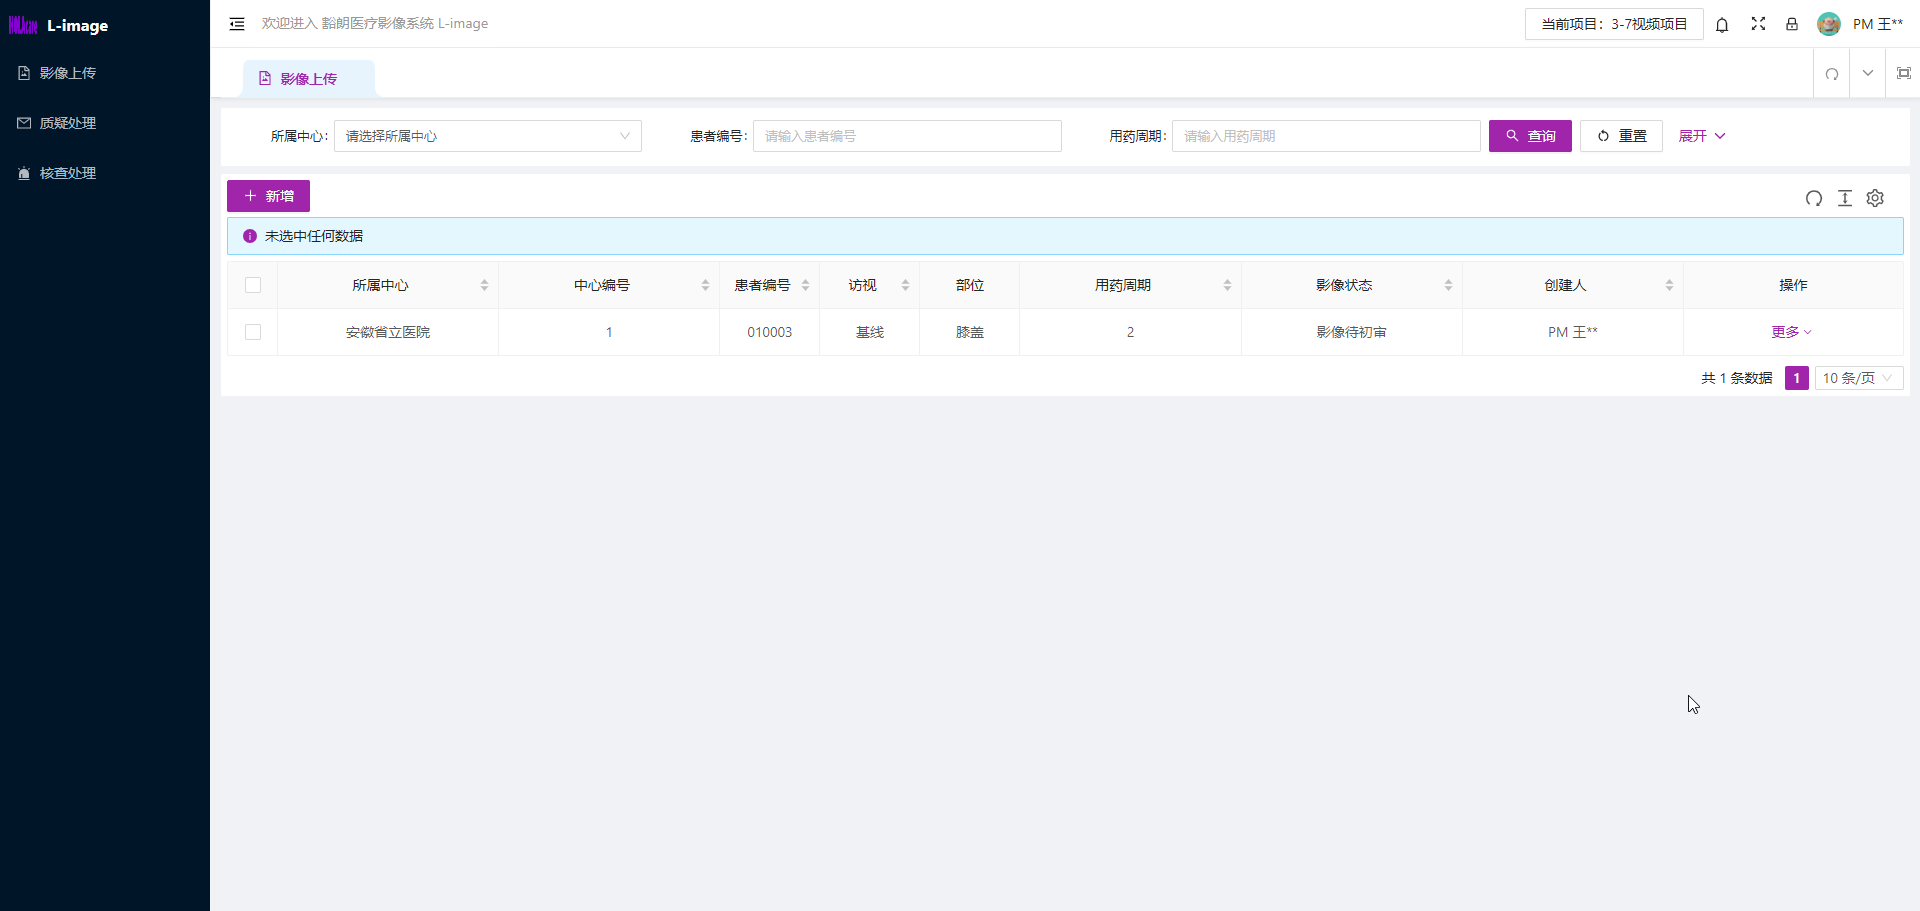

4.熟练使用影像PACS平台的工具及IRC管理工具;